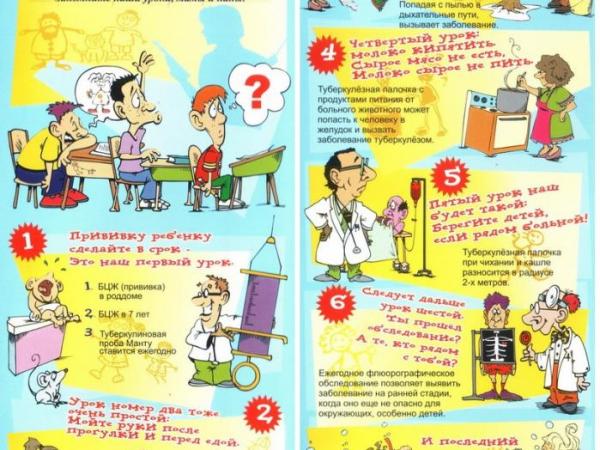

Туберкулез - хроническое инфекционное заболевание, вызываемое микобактериями туберкулеза человеческого или, реже, бычьего вида (последние передаются через молоко и молочные продукты), поражающими в большей мере органы дыхания, а также все органы и системы организма.

Источником инфекции являются больные туберкулезом люди. Наиболее распространенным является воздушный путь заражения. Факторами передачи служат носоглоточная слизь, мокрота и пыль, содержащие бактерии.

Для профилактики туберкулеза очень важно: вести здоровый образ жизни, строго соблюдать санитарно - гигиенические правила:

- мыть руки перед едой,

- не употреблять в пищу немытые овощи и фрукты, а также молочные продукты, не прошедшие санитарный контроль,

Важным моментом для предупреждения туберкулеза является ежегодная постановка пробы Манту, которая дает положительный результат при проникновении патогенных бактерий в организм ребенка